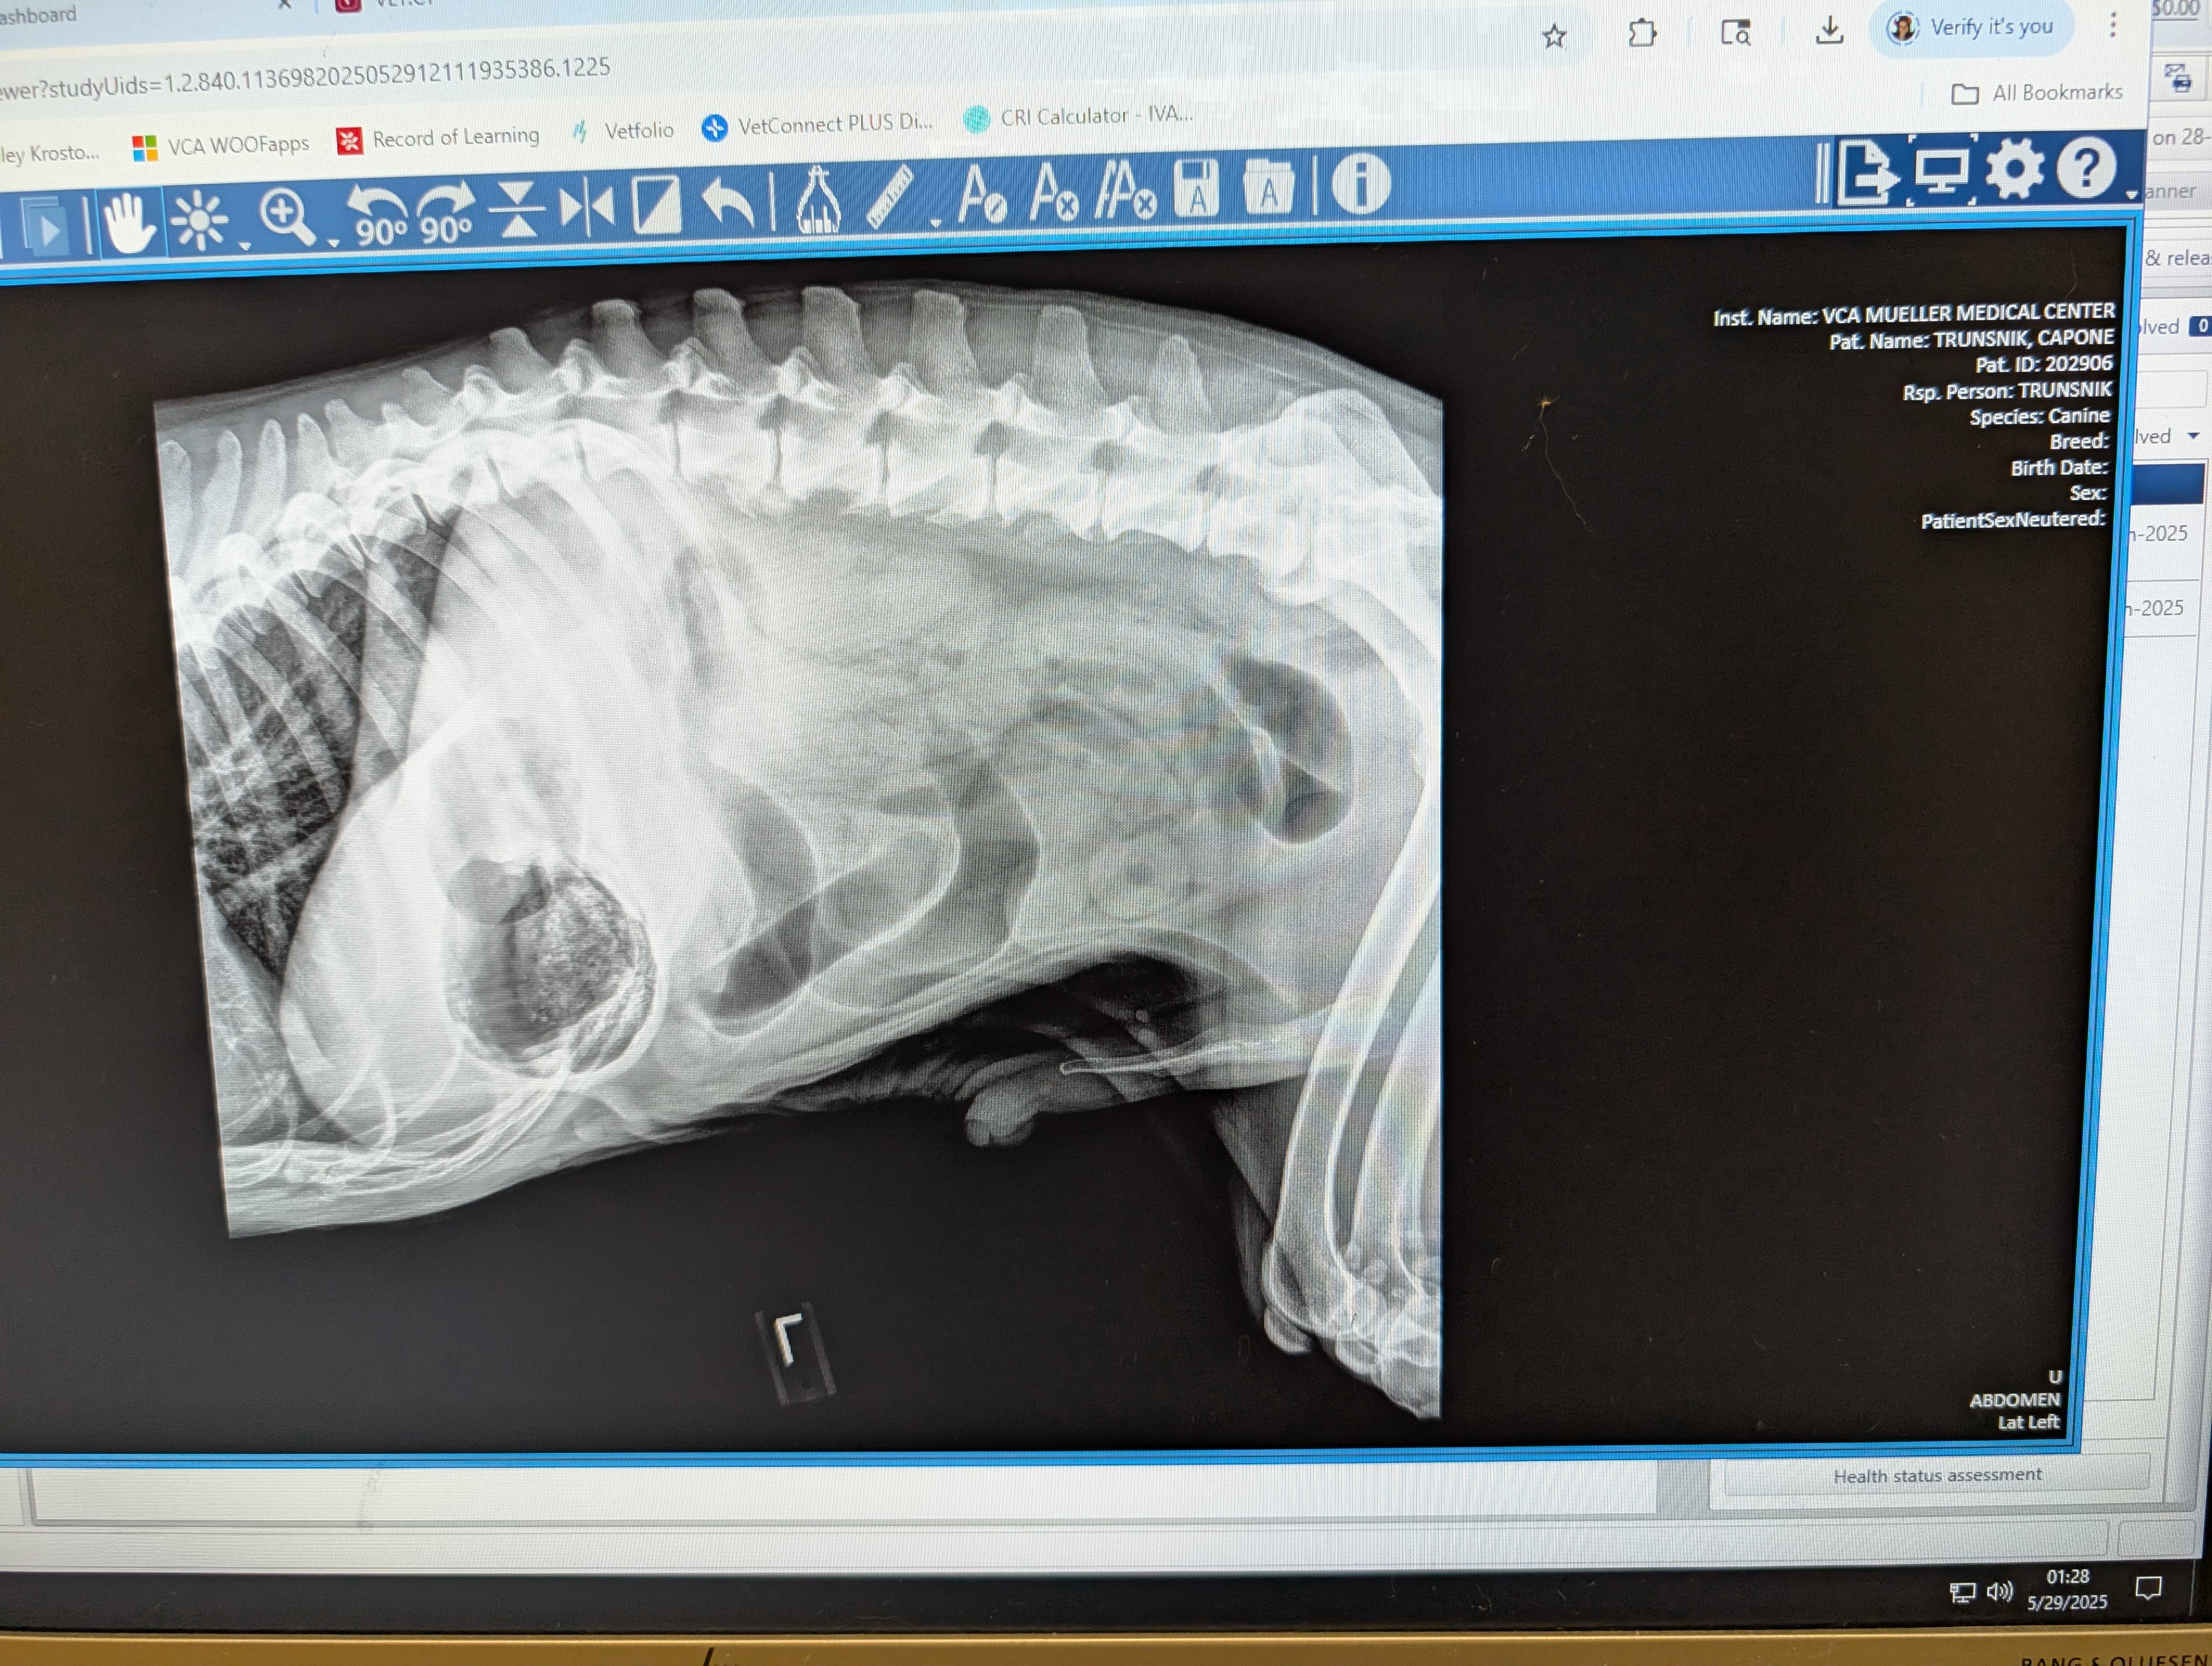

Hello, my name is Destiny and my fiance's name is Natasha she goes by Tasha we are in need of help raising funds to get surgical treatment for our very beloved CAPONE he's our 12 year old senior American Bulldog he's my fiance's BEST FRIEND LITERALLY. Her main man! Everyone who's met Capone falls in love he's just the sweetest boy you could ever meet! A while ago he started acting extremely lethargic, not eating, not sitting down and not very alert at all.. We took him to the vet and they have charged us $1,500 for X-rays and blood work to find that he has a blockage in his stomach and we desperately need help to save him and get him into surgery! Please, if you find it in your heart to help in any way we would greatly appreciate it. My birthday is also tomorrow 05/31 this would be the best birthday gift!! <3 I couldn't imagine not saving him.